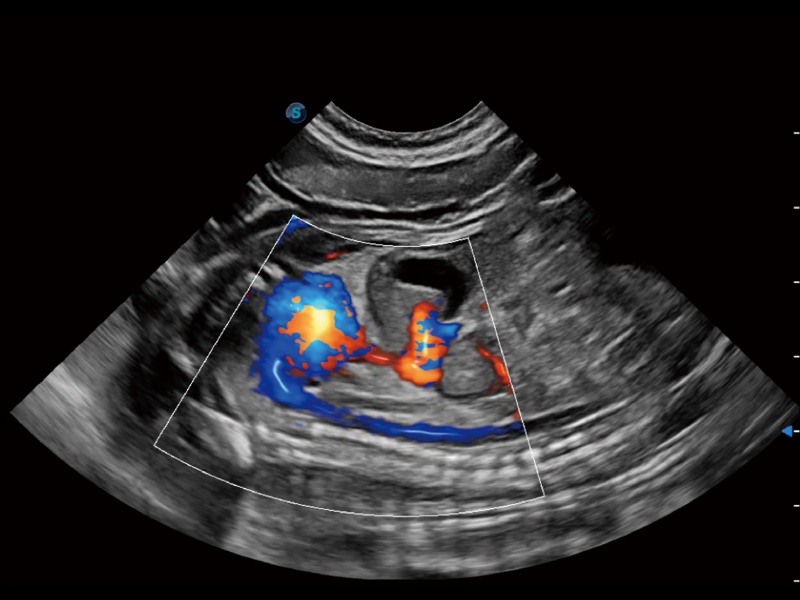

通過色彩血流和實(shí)時寬景相結(jié)合,可觀察到完整的靜脈或動脈的血流,方便醫(yī)生檢查。實(shí)時掃查過程中,如有任何操作失誤也可以很容易地進(jìn)行回掃擦除,而不會中斷掃查。